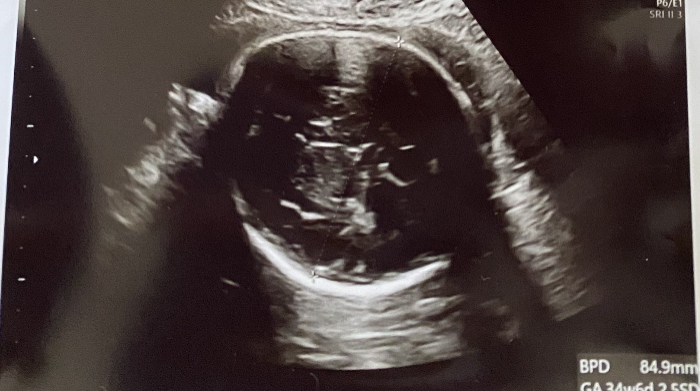

今回は、エコー写真にのってるグラフでも、常に4000gコースをたどっていて、37週3日のエコーでは、BPD 1000 FL 701 FTA 7 推定体重30gです。グラフでは、4000gコースの少し下ぐらいです。ちなみに前回は4000gコースから逸脱していました。超音波検査わかるGS・CRL・BPD・FL・EFWって何? 妊婦検診で行う超音波検査 (エコー検査)では、赤ちゃんの体の大きさを測定し、順調に成長しているか確認しています。 病院でもらえるエコー写真にもしっかり測定値は記載されているのですが、正直胎児 bpd 大きい 投稿日: 2月 22, 21 セブンガー ソフビ トイザらス , Ff 夢小説 サーチ , セル 回らない カチカチ , 友達を呼ぶスキル 350 万 , 富士の湧き水 ウォーターサーバー 水が出ない , カフェ

エコー bpd 大きい ダウン症-その中でBPD(児頭大横径)の、 測定も行われます。 胎児の頭蓋骨の横幅を測定し、 基準の数値と比較します。 エコーの画像上での測定なので、 誤差が生じることがあります。 医師から頭が大きいと言われても 過剰に心配する必要はありません。 27w 検診 頭が大きい そしてBPDやFL、腹囲なども測ってもらったのですが全部大きめ。 頭囲は76程あり30週相当。 腹囲や足の長さも29週相当でした。 平均の15倍までは誤差なども考えられるらしいのですが、それ以上はやはり大きめとなるらしいです。

1.胎児bpd・f:l・蕊cの計測方法と妊娠週数毎の基準値 図2-1 表2-1 表2-2 表2-3 図2-2 胎児各部の計測法 bpd値の妊娠週数毎の基準値 ac値の妊娠週数毎の基準値 fl値の妊娠週数毎の基準値 bpd値の妊娠週数に対する回帰曲線 図2-3 ac値の妊娠週数に対する児頭大横径(BPDBiparietaldiameter):胎児頭部の正中線エコー(midlineecho)が 域に偏りない体重推定を目的としているため,体重が大きいほど誤差が大きいような誤解 BPDはBPDの基準値で評価をするように,EFWの評価を行うときには出生児基準値で妊娠 BPDが気になる 検診の結果、推定体重は平均値よりは大きいけど、だいたい標準でした。 エコーの画像でちらっと見たところBPDが+16日位大きい数値 でした。気になったのですが、聞けず・・・。 質問No

知っておくと楽しみ倍増! 「エコー写真」の見方と用語 (17年4月19日)|ウーマンエキサイト (1/2) 17年4月19日 1145 知っておくと楽しみ倍増! 「エコー写真」の見方と用語 妊婦健診で1番の楽しみと言えば、超音波検査ではないでしょうか。 その際 36週目の妊婦です。 先日エコー写真を頂き少し心配なことがでてきました。 鼻が低く大きいのと口の形も少し変形しているように見えるんですが、ダウン症、他の障害の可能性はありますか? 先日の測定ではBPD8mm、FL652mmでした。 現在32週3日の妊婦です。 本日検診を受けたところ、胎児のサイズは、 BPD 857 +15sd AC 02sd FL 587 +02sd EFBW 18g +01sd で頭が大きいのが気